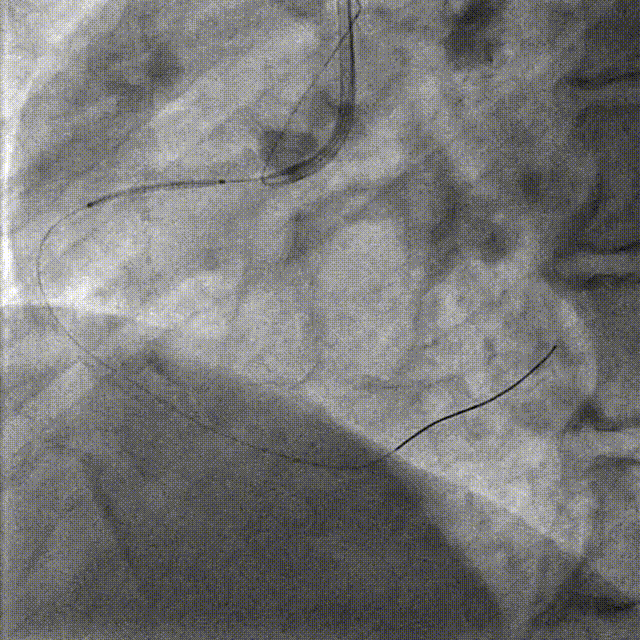

PCI-RCA TR, 7F JR4.0 ROTA with 2.0mm burr

Angiography post-ROTA

Lesion preparation NC 2.5*12mm → Cutting balloon 4.0*10mm @ 12atm

Angiography & DCB Angioplasty DCB 4.0*20mm @ 8atm, 60s

DES Deployment & Optimization DES 4.0*20mm → NC 4.0*12mm @ 20atm

Final Results